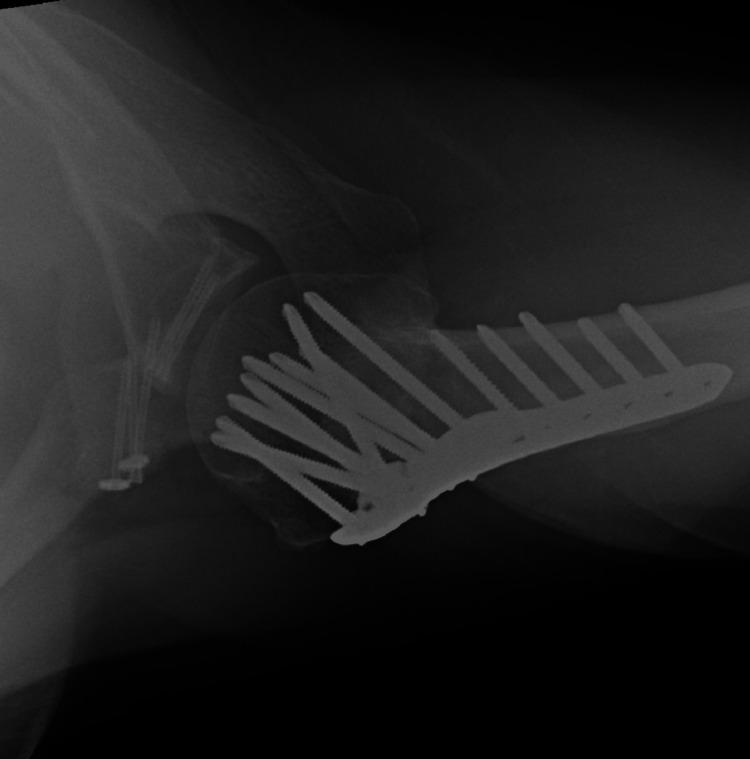

Fractures of the proximal humerus are common injuries with a bimodal age distribution. They usually present in younger patients after high-energy trauma and in elderly patients after lower-energy trauma. Fractures of the proximal humerus are rarely associated with concomitant fractures of the glenoid, and this is a complex injury pattern that indicates the presence of significant instability. Such injuries are usually treated surgically. Even more rarely, patients may present with proximal humerus fractures and fractures of the coracoid process. A male patient presented to our emergency department (ED) after a fall off the loading platform of his heavy goods vehicle (HGV), resulting in a right shoulder injury. During his initial assessment in ED, a computerised tomography (CT) scan demonstrated the presence of a comminuted proximal humerus fracture, a comminuted anterior glenoid wall fracture, and a coracoid process displaced fracture. Surgical fixation of all three fractures was undertaken in the same sitting. This is the first case described in the literature with a combination of the above injuries and serves as a reminder that as trauma complexity and incidence continue to increase, we should maintain a high index of diagnostic suspicion when dealing with such patients. Furthermore, we present our treatment approach for this case and the rationale behind it.

肱骨近端骨折是常见损伤,具有双峰年龄分布。它们通常在年轻患者遭受高能创伤后以及老年患者遭受低能创伤后出现。肱骨近端骨折很少与肩胛盂骨折同时发生,而这种复杂的损伤模式表明存在明显的不稳定。此类损伤通常采用手术治疗。更罕见的是,患者可能同时出现肱骨近端骨折和喙突骨折。一名男性患者从他的重型货车装载平台上跌落后来到我们的急诊科,导致右肩部受伤。在急诊科对他进行初步评估期间,计算机断层扫描(CT)显示存在肱骨近端粉碎性骨折、肩胛盂前壁粉碎性骨折以及喙突移位骨折。在同一次手术中对所有三处骨折进行了手术固定。这是文献中描述的首例上述损伤组合的病例,提醒我们随着创伤复杂性和发生率不断增加,在处理此类患者时应保持高度的诊断怀疑指数。此外,我们展示了针对该病例的治疗方法及其背后的原理。